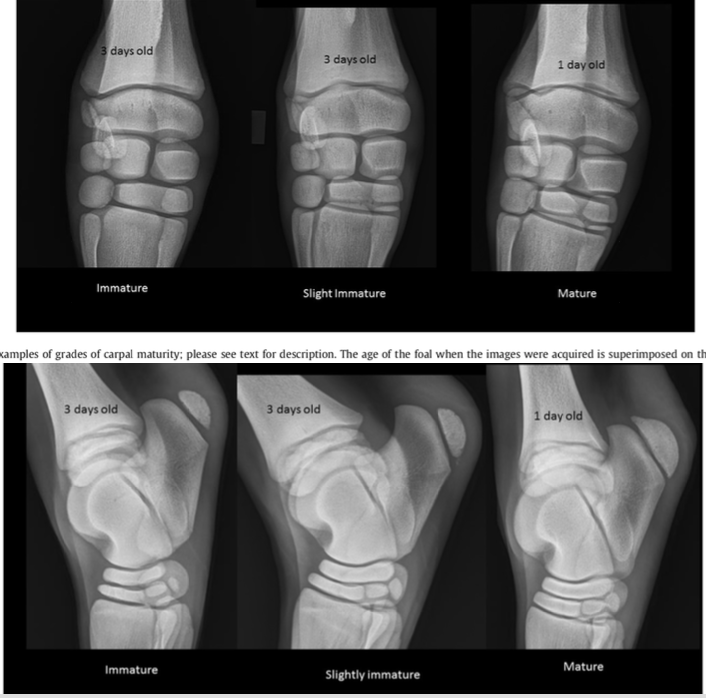

Describe the incomplete ossification grading described by Stanshi 2018 (JEVS)

CARPUS

Mature carpus: The margins of the cuboidal bones are straight with square corners. The dense palmar process of the third carpal bone (C3) is visible through the dorsal aspect. The lateral styloid process (LSP) is triangular, with a flat distal surface that angles proximally at the lateral aspect. The fourth metacarpal bone and fourth carpal bone (C4) have flat surfaces. A trabecular bone pattern is apparent in all carpal bones.

Slightly immature carpus: The cuboidal bone margins have curved corners and slightly rounded facets. The palmar process of C3 is faint. The LSP is oval, with no obvious flat distal surface. The distal margin of C4 and the proximal fourth metacarpal bone are rounded. A trabecular bone pattern is variably apparent.

Immature carpus: The margins of most carpal bones are round, especially the ulnar and C4, and the palmar process of C3 is indistinct. The LSP is oval, and there is a large space between it and the proximal margin of the ulnar carpal bone. C4 is almost round, and the proximal margin of the fourth metacarpal bone is rounded. The cuboidal bones show very little trabecular detail.

TARSUS

Mature tarsus: The dorsal margins of the central (TC) and third (T3) tarsal bones are slightly rounded, and the joint spaces between talus, TC, T3, and the fourth metatarsus are thin with parallel surfaces. The center of TC and T3 has a homogeneous trabecular density, and the articular surfaces have thin dense margins. The lateral trochlear ridge of the talus has formed a distal notch, and T1/2 are fused. The plantar calcaneal apophysis reaches the plantar calcaneal margin, and the distal calcaneal margin is flat

Slightly immature tarsus: The dorsal corners of TC and T3 are curved, resulting in a wider joint space at the dorsal aspect. The center of TC and T3 is homogeneous in density and lacks an obvious trabecular appearance; a dense subchondral margin is not apparent. The distal lateral trochlear ridge is horizontal, and fusion of T1&2 is indistinct or absent. Mineralisation of the calcaneal apophysis does not reach the plantar calcaneal margin, and the distal calcaneal facet is rounded.

Immature tarsus: The dorsal margin of TC and T3 are curved or pointed, resulting in a very wide dorsal joint space. The center of TC and T3 has an indistinct bone pattern that does not resemble trabecular or cortical bone. The joint surfaces can be irregular, and the bone density is heterogenous. The distal lateral trochlear ridge is angled proximally, and T1&2 are not fused. Mineralisation of the calcaneal apophysis is reduced, and the distal calcaneal facet is round. A foal with a focal area of severely reduced mineralization anywhere in the cuboidal bones would be graded as immature